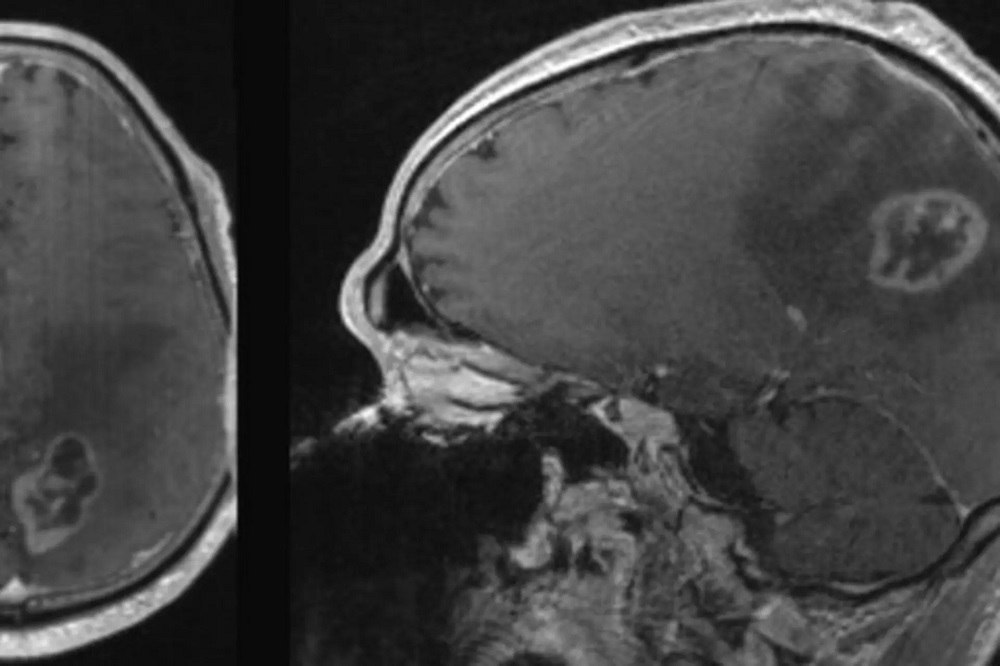

بەڕێوبەری گشتی تەندرووستی دهۆک دەڵێت: "نەخۆشخانەی ئومێد تایبەت بە چارەسەری نەخۆشی شێرپەنجە لە قۆناغی کۆتایی دایە، لەم نزیکانە تەواو دەبێت و دەکەوێتە خزمەت خەڵکی پارێزگای دهۆک، ئەو نەخۆشخانەیە زۆر باش و گرینگە، چیتر پێویستمان بە دەرەوەی پارێزگای دهۆک نابێت."

د.ئەفراسیاب مووسا، بەڕێوبەری گشتی تەندرووستی دهۆک، ڕایگەیاند "نەخۆشخانەی ئومێد تایبەت بە چارەسەری نەخۆشی شێرپەنجە لە دهۆک کۆتایی بە کارەکانی هاتووە، ئێستا کار بۆ کردنەوەی نەخۆشخانەکە دەکەین، هەر کاتێک کارەکانی تەواو بوو دەکرێتەوە و دەکەوێتە خزمەت هاووڵاتییان، لەم مانگە پشووی زۆر هەبوو، ئێستا کاری بەردەوام دەکرێت و تەواو بێت و دەکرێتەوە، تەنیا هەندێک ئامێر مابوو، دوای جەژن تەواو دەکرێت و دەکەوێتە خزمەت خەڵکی دهۆک."

د.ئەفراسیاب مووسا ووتیشی "بە تەواوبوونی نەخۆشخانەکە خزمەتێکی باشی نەخۆشانی شێرپەنجە لە پارێزگای دهۆک دەکرێت، دوای جەژن نەخۆشخانە ١٦٠ قەرەوێلەییەکە دەکرێتەوە و یەکێک دەبێت لە نەخۆشخانە گرینگەکانی پارێزگاکە و چیتر پێویستمان بە شارەکانی دیکە نابێت بۆ ئەوەی نەخۆشەکانمان بچن لەوێ چارەسەری وەربگرن، لەو نەخۆشخانەیە چارەسەر دەکرێن."